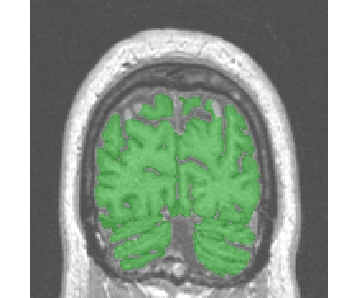

Strange results

the numerous refinements of the simple erosion/dilation procedure allowing robustness to a wide range of images may sometime create strange problems. For instance, with "Robust..." procedures, a piece of white matter may be deleted in corpus callosum and brain stem:

The best solution is the use of the simplest variants:

"Fast (2mm erosion)"

"Fast (2.5mm erosion)"

"Fast (3mm erosion)"